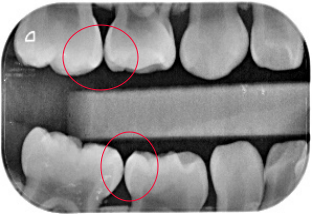

uu们能看出来龋坏吗我怀疑是邻面龋

图片尺寸1080x810